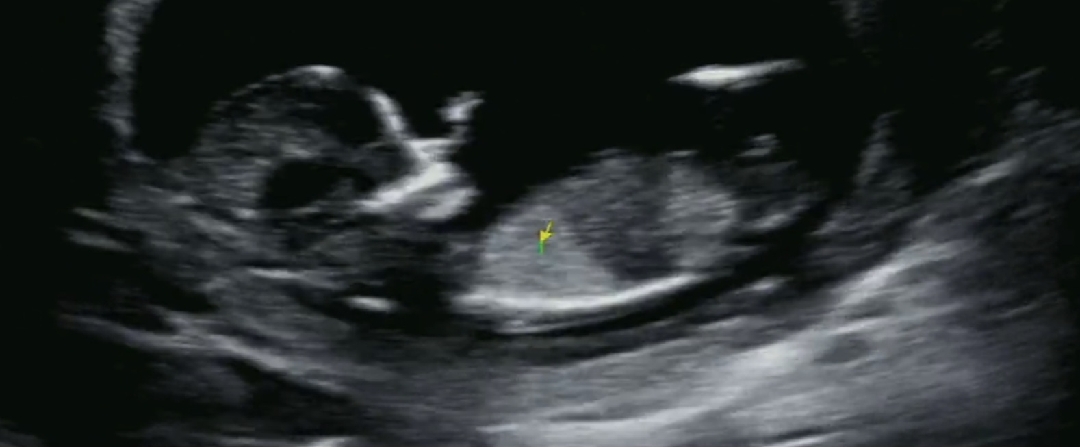

12주 초음파인데 각도법 예상되시나요?